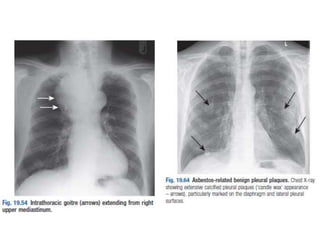

• Trachea

• Central? (Midway

between the clavicular

heads)

• Paratracheal mass?

Goitre?